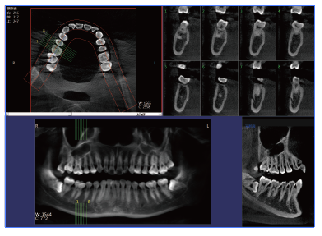

PLX3000A口腔CBCT—普愛醫療

一、口腔cbct的優勢1、射線劑量低,可廣泛應用于口腔頜面外科,正畸科,正頜外科和種科等。

2、在視野選擇上面,圖像合成等口腔專業所學個性化的圖像生成方面,口腔cbct的優勢更為凸顯,其發展空間較大。